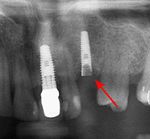

قبل زراعة الأسنان، يطلب من المريض اجراء فحص تصوير للأسنان، وعادة يطلب اجراء صورة خاصة (صورة أشعة بانوراما للأسنان) أو حتى فحص التصوير المقطعي المحوسب (CT)، للكشف والتشخيص عن حالات الأسنان التي ليس بالامكان رؤيتها من خلال الفحص الاعتيادي.